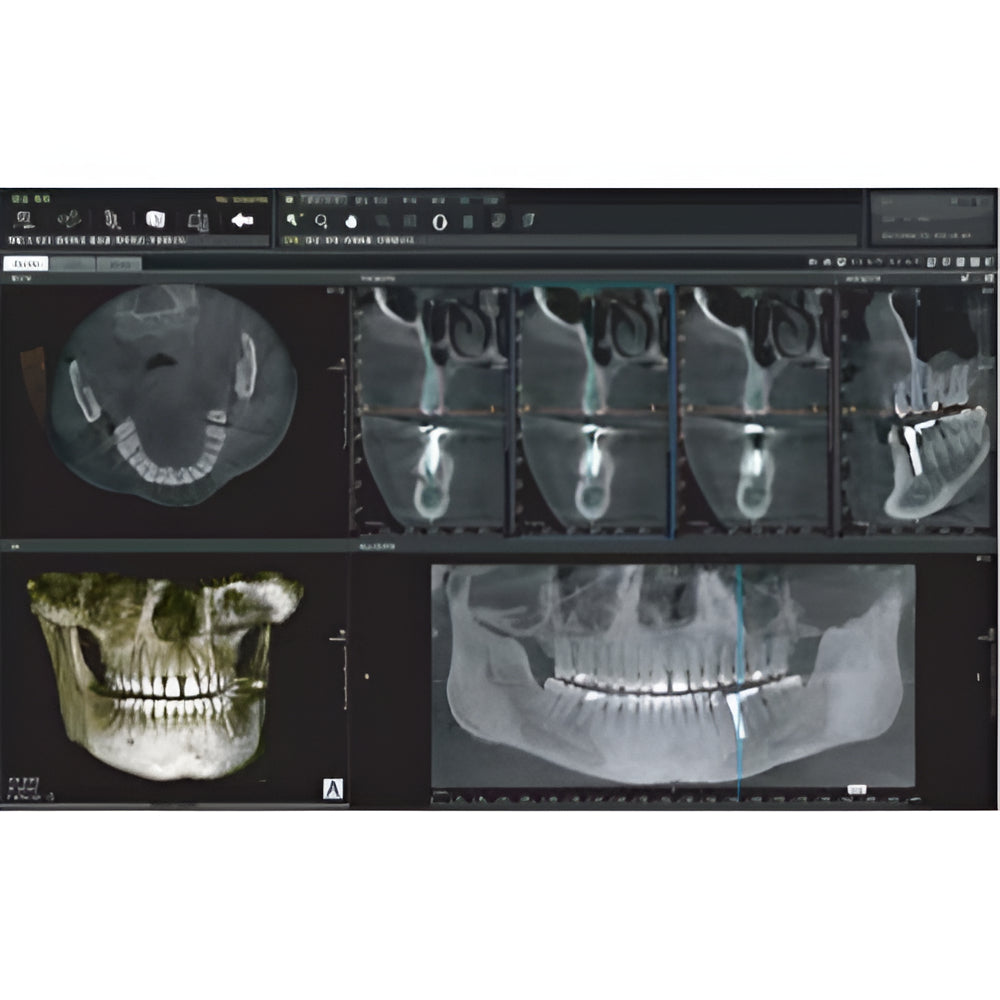

Papaya uses the CdTe sensor, which improves image quality while keeping radiation exposure to a minimum. The CdTe (Cadimium telluride) sensor overcomes the limitations of a CMOS sensor to always produce high quality images.

- 3D imaging software

- Field Of View: 4x5, 7x7, 8x8, 14x8, 14x14

- Multi-FOV selection

- 7.7 sec fast scan for 3D image

- Large FOV